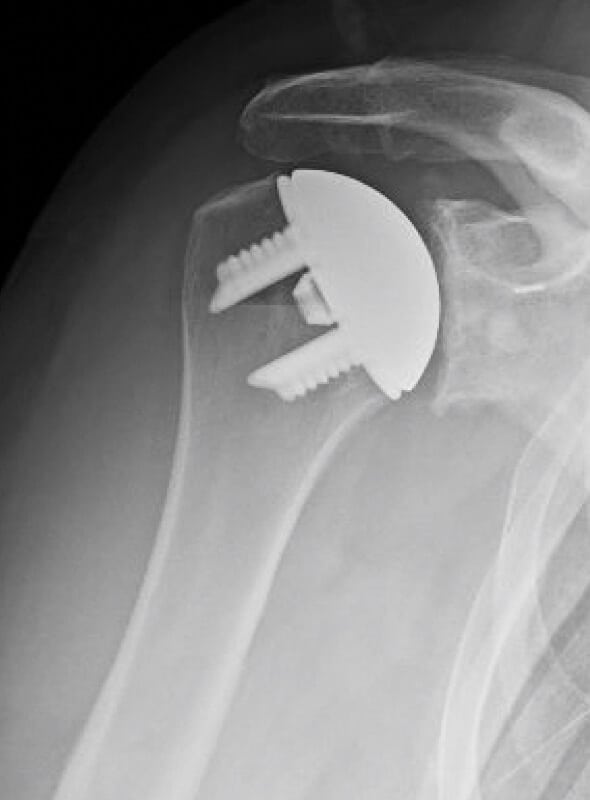

DePuy, Icon

Selected